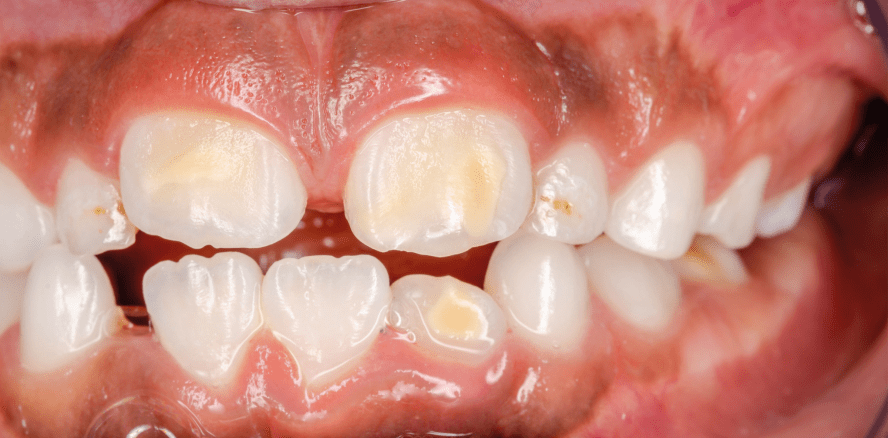

Die MIH stellt eine entwicklungsbedingte Erkrankung der Zahnhartsubstanz dar, die durch qualitative Schmelzdefekte in Form verringert mineralisierter, fehlstrukturierter Schmelzanteile gekennzeichnet ist. Diese führen in der einfachsten Form zu weißlichen Opazitäten, bräunlichen Verfärbungen oder Porositäten in schwereren Verlaufsformen, aber auch zu fortschreitenden Schmelzaus- und -abbrüchen bis hin zu umfangreichen Abrasionen. Häufig leiden die betroffenen Kinder unter ausgeprägten Hypersensibilitäten bis hin zu eingeschränkt möglicher, sehr schmerzhafter Mundhygiene und unter Umständen rasch fortschreitender Karies. Zumeist sind die (ersten) Molaren und klassischerweise auch (gehäuft) die oberen mittleren Frontzähne betroffen. Im Oberkiefer ist das Krankheitsbild häufiger als im Unterkiefer, jedoch können jüngst auch andere Zähne (seitliche Schneidezähne, Eckzähne, 2. Molaren) und auch bereits Milchzähne betroffen sein.